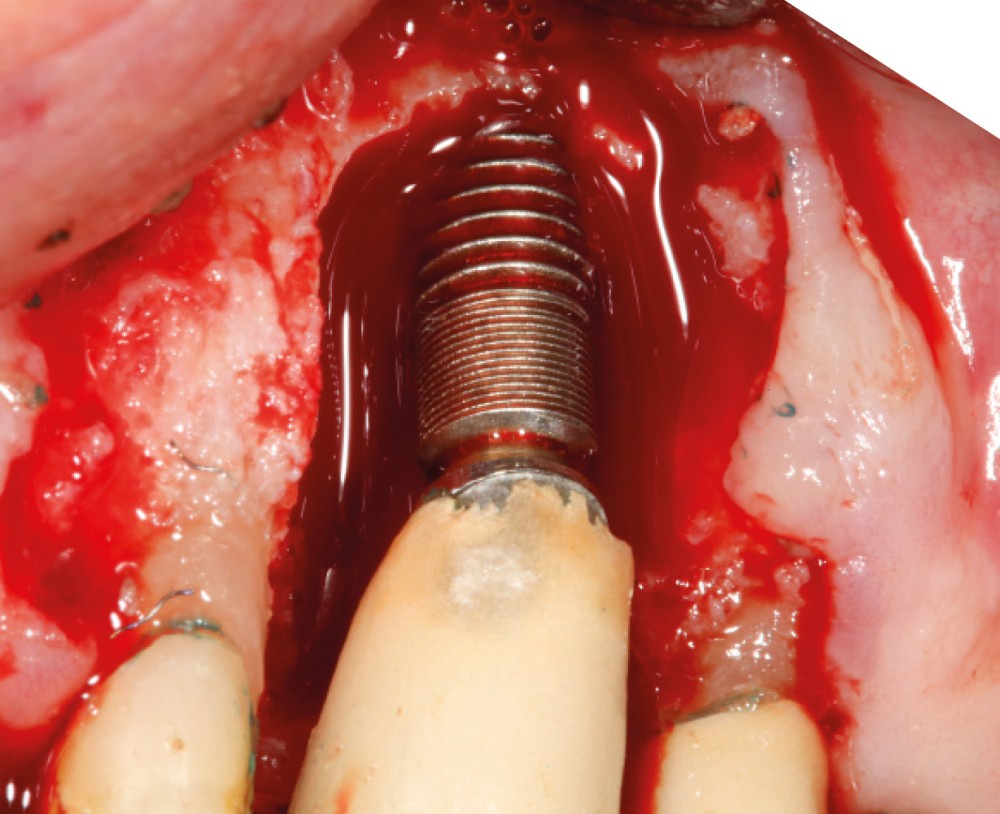

Le patient

- 70 ans

- Pas d’antécédents médicaux

- Ne fume pas

- Hygiène correcte

L’implant

- Site 23

- Mis en place il y a 12 ans